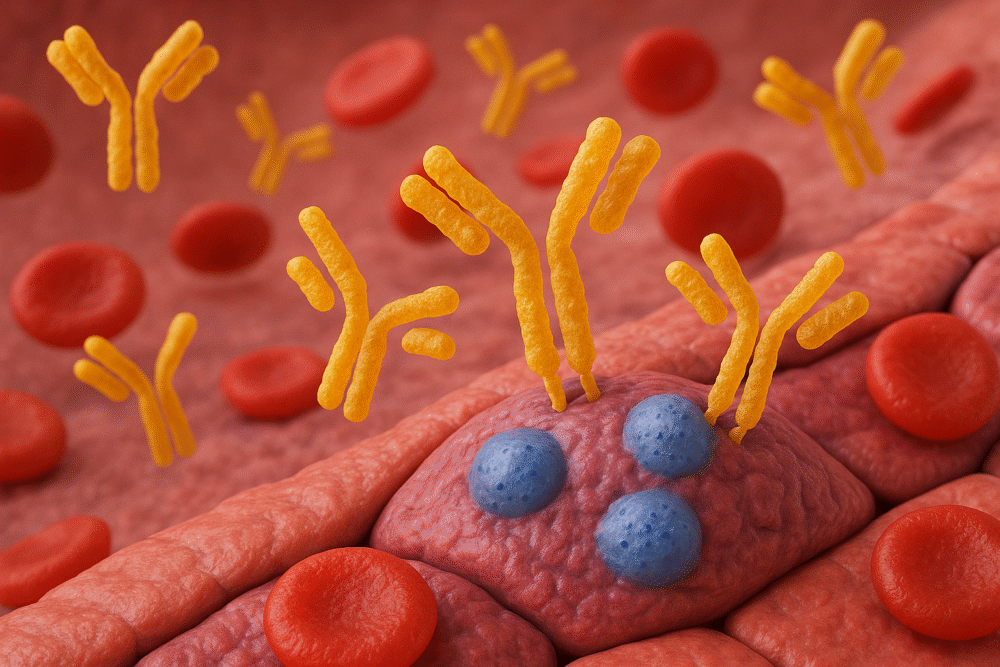

Anticorpi anti-celulă endotelială vasculară. Ce semnifică și când îi dozăm

Celulele endoteliale sunt celulele care căptușesc interiorul vaselor de sânge, având un rol esențial în…